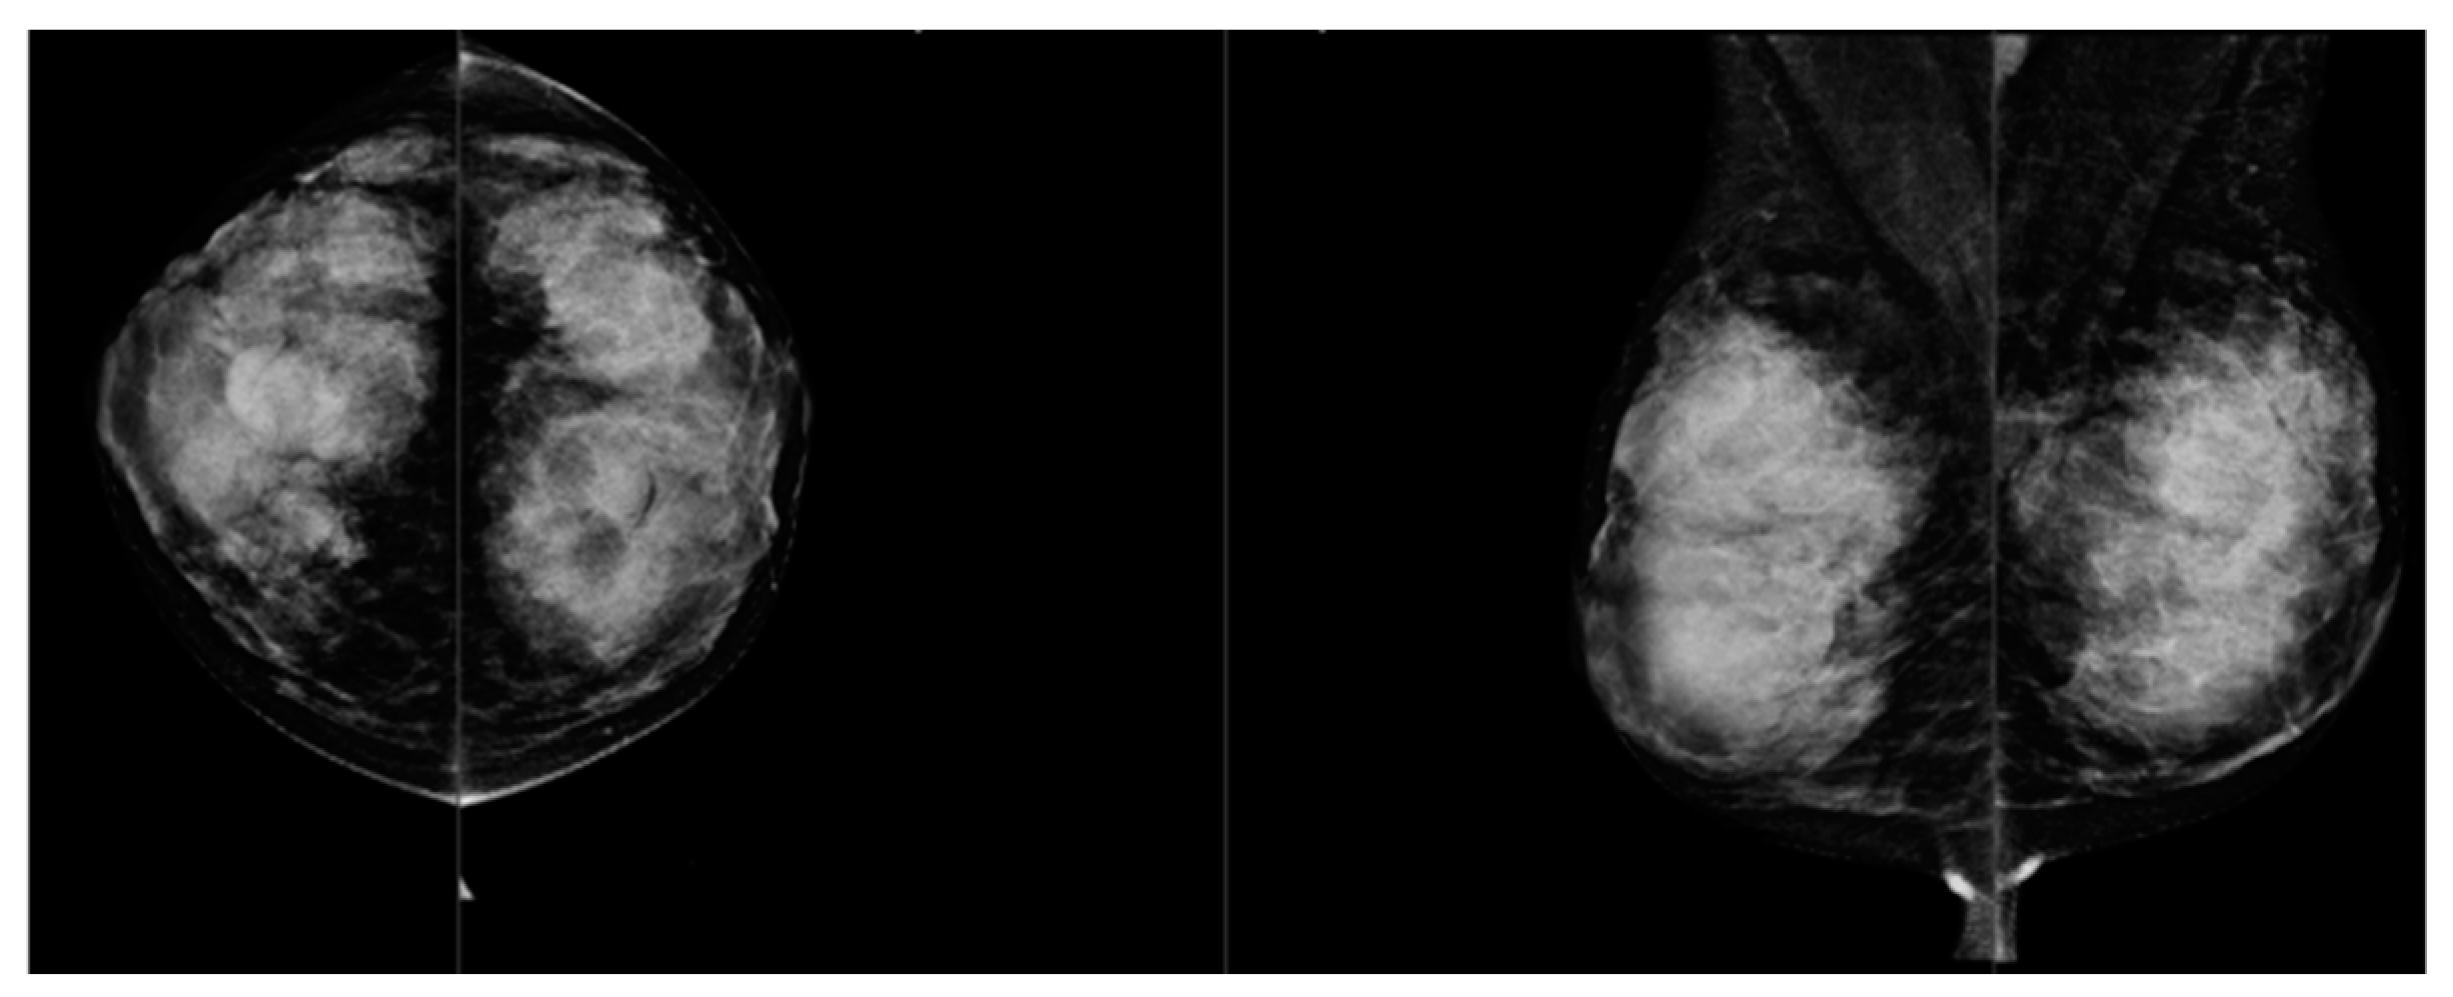

Comparison of Visual and Quantra Software Mammographic Density Assessment According to BI-RADS® in 2D and 3D Images

2. Materials and Methods

2.2. Image Acquisition

2.3. Software for Automatic Breast Density Assessment

| BI-RADS Category: | Reader 1 (R1) | Reader 2 (R2) | Mean R1-R2 | Quantra Software (R3) |

| A | 1646 (33%) | 1538 (30%) | 1592 (32%) | 673 (13%) |

| B | 2241 (45%) | 2364 (48%) | 2303 (46%) | 2131 (43%) |

| C | 915 (18%) | 891 (18%) | 903 (18%) | 1728 (34%) |

| D | 178 (4%) | 179 (4%) | 179 (4%) | 477 (10%) |

| Intraclass Correlation Coefficients | Results |

| ICC (R1 vs. R3) | 0.725 |

| ICC (R2 vs. R3) | 0.713 |

| ICC (R1 vs. R2) | 0.712 |

| ICC (meanR1-R2 vs. R3) | 0.793 |